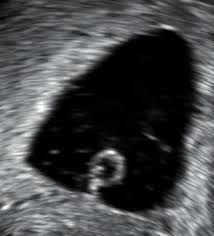

A blighted ovum, also called an anembryonic pregnancy, occurs when an early embryo never develops or stops developing, is resorbed and leaves an empty gestational sac. The reason this occurs is often unknown, but it may be due to chromosomal abnormalities in the fertilized egg.